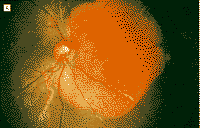

图5 1997年2月上(A)下(B)眼病变的眼底镜所见。(注)根据图片所示,上(A)和下(B)眼,似应为右(A),和左(B)眼

脉络膜骨瘤是脉络膜的一种良性骨性肿瘤,典型地见于10多岁至20多岁健康年轻女性。约25%的患者中,这种异常为双侧性1,2。此肿瘤一般发展并不快2~4。计算机断层扫描检查及A超和B超检查显示该肿瘤是一典型的脉络膜骨瘤。但是,此肿瘤的迅速增大是个例外。该肿瘤是在检查斜视时意外地被发现;与其它报告相比,这些早期肿瘤很小,而且患者很年轻。据我们所知,这是所报告的有此情况的最年轻患者。我们认为发生在小年龄的骨瘤可迅速增大。